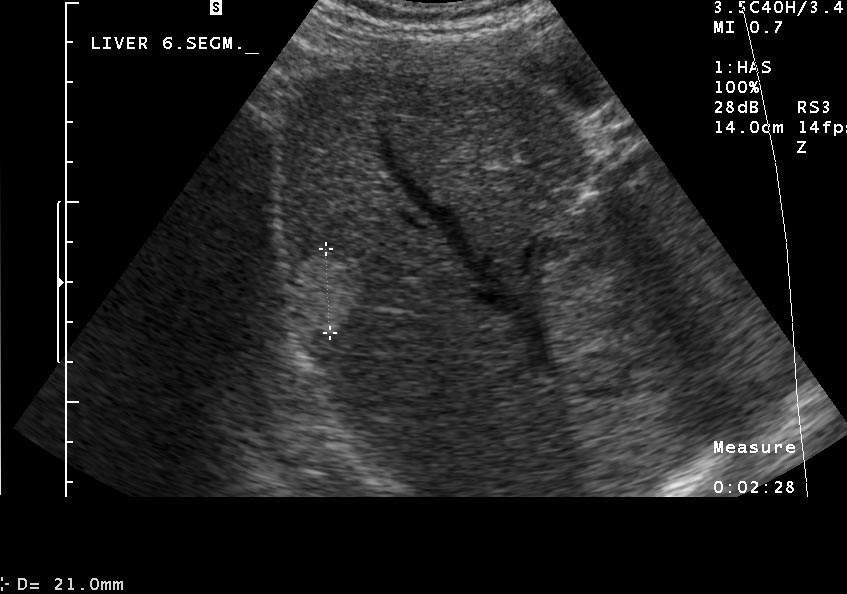

Typical apprearence includes a well defined, hyperechoic solide lesion measuring usually less than 2 cm in diameter (Figure 18).

Figure 18: Typical US image of a hemangioma in the sixth segment of the liver

In case of an atypical hemangioma (inhomogeous, mixed echostructure or hypoechoic appearence) additional imaging methods (multiphase MDCT, MRI) can be necessary, in addition in certain cases US guided biopsy can not be avoided in order to achieve the final diagnosis.

MRI is only needed in case of "atypical" hemangiomas, since ultrasound is the best imaging method for diagnosing the hemangioma. If the ultrasound finding is uncertain, dynamic CT (Figure 19, 20), afterwards nuclear imaging and biopsy are the appropriate choices.